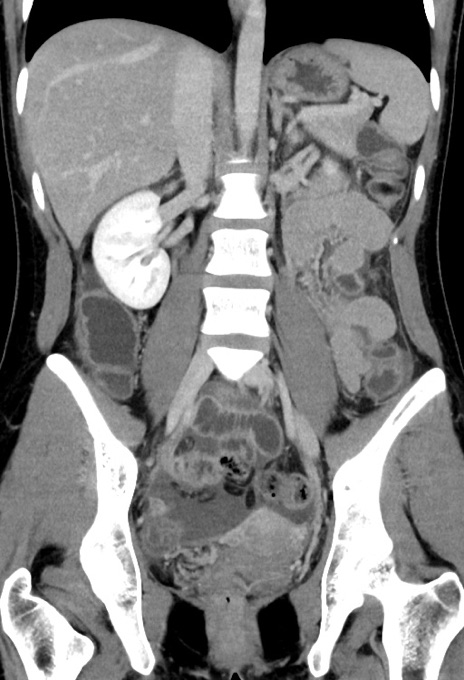

症例17(冠状断像)

【症例】20歳代女性

【主訴】嘔吐、下腹部痛

【現病歴】昨日夕食後に嘔吐し下腹部痛が出現。本日になっても嘔吐持続し改善しないため来院。

【身体所見】意識清明、BT 37.2℃、BP 108/67mmHg、腹部:平坦、やや硬、下腹部正中から右にかけて圧痛あり、反跳痛軽度あり、tapping pain(+)。

【データ】WBC 13600、CRP 14.94

横断像